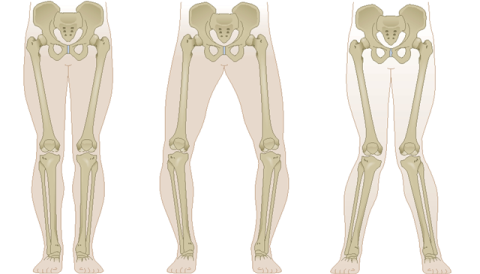

Το παιδί σας έχει παραπεμφθεί σε μας με ραιβογονία ή βλαισογονία. Αυτό το σημείωμα έχει φτιαχτεί για να σας βοηθήσει να μάθετε για αυτές τις δύο καταστάσεις που σχετίζονται μεταξύ τους. Ραιβογονία σημαίνει ότι τα γόνατα έχουν κενό μεταξύ τους όταν τα πόδια (αστράγαλοι) έρχονται σε επαφή το ένα με το άλλο. Βλαισογονία παρατηρείται όταν υπάρχει κενό ανάμεσα στους αστραγάλους όταν τα γόνατα ακουμπούν το ένα το άλλο.

ΕΙΝΑΙ Η ΒΛΑΙΣΟΓΟΝΙΑ ΚΑΙ ΡΑΙΒΟΓΟΝΙΑ ΑΝΩΜΑΛΙΕΣ?

ΟΧΙ ΣΤΑ ΠΕΡΙΣΣΟΤΕΡΑ ΠΑΙΔΙΑ.